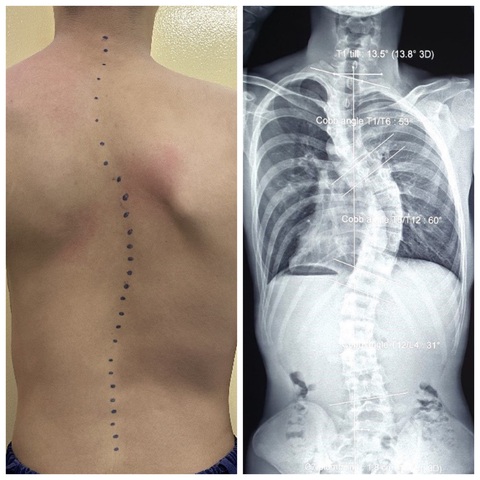

Sinh viên V.L.A. (nữ, 19 tuổi) bị vẹo cột sống ngực thắt lưng nặng với góc 44 độ, mất độ ưỡn sinh lý cột sống cổ - Ảnh: Bác sĩ cung cấp

Trường hợp khác là bệnh nhân L.Đ. (nam, 18 tuổi) trong tình trạng khá nghiêm trọng: vai trái lệch cao gần 5cm so với vai phải, lồng ngực biến dạng, cột sống cong chữ S, nặng nhất ở đoạn ngực, lệch vẹo khung chậu.

Trên phim X-quang vẹo cột sống đoạn ngực chữ S rất nặng với góc T1-T6 là 53 độ, T6-T12 là 60 độ.

Bệnh nhân L.Đ. (nam, 18 tuổi) bị vẹo cột sống đoạn ngực chữ S rất nặng, vai trái lệch cao gần 5cm so với vai phải, lồng ngực biến dạng - Ảnh: Bác sĩ cung cấp